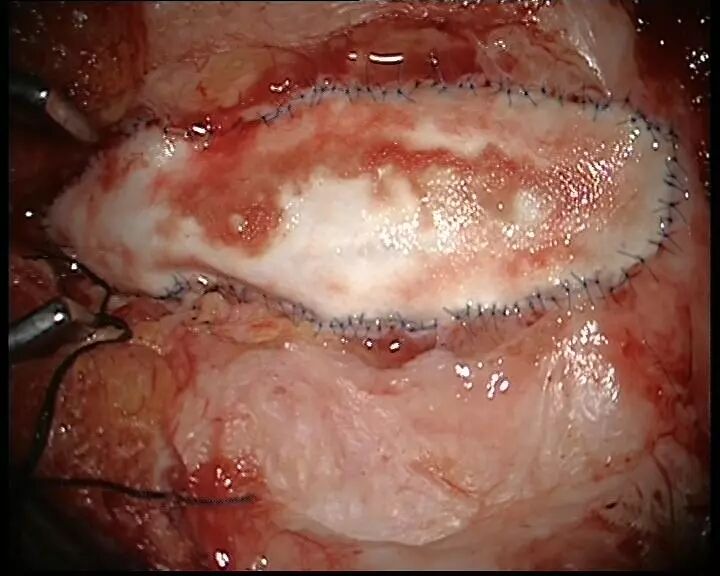

5. 扩大修补硬脊膜。技术要点:扩大并无张力下修补,以6-0prolene线硬脊膜包边Asculap Neuro-Patch补片间断包边严密缝合。

我们对使用过Neuro-Patch补片修补过硬膜的患者进行二次开颅手术,术中发现该补片确实极少和脑表面发生粘连。这一特点是脊柱裂手术中预防粘连是极为珍贵的。由于该补片的变形适应性一般,其是否适用于脊柱手术呢?我们经过2年多的摸索,实验了包括间断缝合,连续缝合、连续锁边缝合,连续包边缝合,间断包边缝合等方法。最终证实间断包边缝合的方法术后脑脊液漏的发生率最低,补片的塑形效果最好。